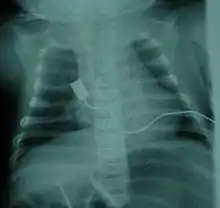

The respiratory system is the most common system to be affected and the complications are the leading cause of death in SMA types 0/1 and 2. SMA type 3 can have similar respiratory problems, but it is more rare.[23] The complications that arise are due to weakened intercostal muscles because of the lack of stimulation from the nerve. The diaphragm is less affected than the intercostal muscles.[23] Once weakened, the muscles never fully recover the same functional capacity to help in breathing and coughing as well as other functions. Therefore, breathing is more difficult and pose a risk of not getting enough oxygen/shallow breathing and insufficient clearance of airway secretions[32]: 378 . Swallowing muscles can be affected, leading to aspiration coupled with a poor coughing mechanism increases the likelihood of infection/pneumonia.[55][56] Mobilizing and clearing secretions involve manual or mechanical chest physiotherapy with postural drainage, and manual or mechanical cough assistance device. To assist in breathing, non-invasive ventilation (BiPAP) is frequently used and tracheostomy may be sometimes performed in more severe cases[57]